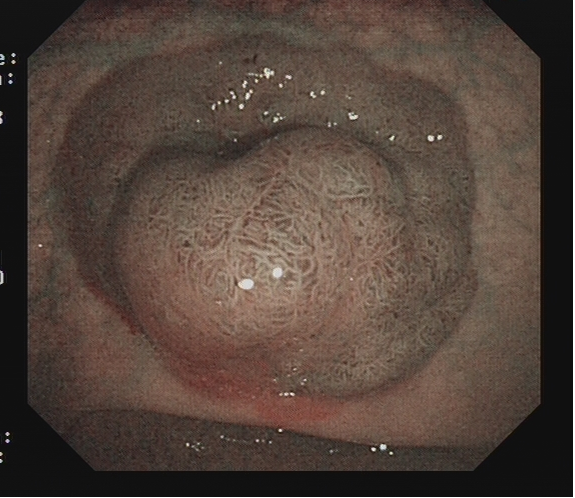

适用于不同大小隆起型病变Ⅰp型、Ⅰsp 型以及小型(<2 cm)Ⅰs型(具体分型标准可参照内镜发现消化道早癌,分型太多不知道怎么判断?这篇文章讲清楚了)病变的切除。小型Ⅰp型病变,圈套切除相对简单,可采用冷或热圈套切除,切除时应在保证完整切除病变同时,保留一定长度的蒂部或与肠壁保持一定距离,收紧圈套后,应抖动圈套器,观察有无周围正常肠黏膜一并套入,防止损伤肠壁。

图2 小型Ⅰsp 型病变热圈套切除示意图